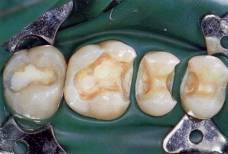

Wkłady koronowe - osadzone w pojedynczym zębie, zastępują tradycyjne wypełnienia "plomby", są szczególnie polecane do zębów bocznych ze względu na dużą wytrzymałość.

Wkłady koronowe wykonywane są:

Przygotowane ubytki do

cementowania wkładów |